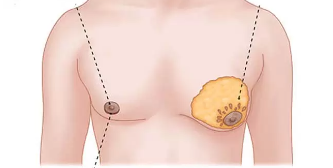

نکاتی چند در مورد تکامل و آناتومی پستان

در این مطلب دکتر مهدی جعفری فوق تخصص جراحی پلاستیک و زیبایی و بهترین جراح زیبایی به ترجمه تخصصی مقاله ای معتبر در خصوص آناتومی پستان در زمینه های مربوط به جراحی سینه ، پروتز سینه و لیفت سینه از منابع معتبر پرداخته اند.

کوچک کردن سینه آقایان یا ژنیکوماتسی

بزرگ بودن سینه در آقایان (ژنیکوماستی) مشکلی است که به دلایل مختلفی بروز می کند، بزرگ بودن سینه علاوه بر تخریب زیبایی ظاهری و اندام ممکن است ایجاد درد و تورم بنماید که منجر به تقاضای شخص به کوچک کردن سینه می گردد. این مشکل که به دلیل رشد غیر طبیعی غدد پستانی در مردان اتفاق می افتد، در بسیاری از موارد منجر به بزرگ شدن بیش از اندازه سینه و در نهایت افتادگی آن می شود، این مشکل به صورت شایع در نوجوانان دیده می شود و ممکن است در نوزادان و یا افراد مسن نیز بروز نماید.ژنیکوماستی که نوعی بیماری یا اختلال متابولیکی می باشد به راحتی توسط جراحی ژنیکوماستی قابل درمان بوده و باعث بهبود ظاهر و کاهش درد و تورمات در بدن فرد می شود

بازسازی سینه در جراحی زیبایی سینه با پروتز

زمانی که عمل بازسازی سینه یا جراحی سینه صورت می گیرد هدف اصلاح نمودن تغییرات بدن و یا برگرداندن سلامتی به شخص می باشد. امروزه بسیاری از بانوان جهت درمان سرطان سینه به انجام جراحی سینه می پردازند ، در جراحی سینه بخش زیادی از بافت پستان حفظ می شود ، در جراحی سینه فقط بخش کوچکی از سینه را بر می دارند.

کوچک کردن سینه ماموپلاستی

ماموپلاستی یکی از انواع جراحی پلاستیک است که هدف آن تغییر سایز پستان (کوچک کردن سینه) بوده تا با تغییر فرم و کاهش سایز آنها به زیبایی اندام کمک کند بنابراین میتوان ماموپلاستی را یکی از انواع جراحی زیبایی به شمار آورد،گرچه در مواردي كه سينه خيلي بزرگ است و باعث مشكلات ساييدگي مهره هاي گردني مي شود،مي تواند درماني نيز محسوب شود.

رفع افتادگی سینه با لیفت سینه

یکی از شایع ترین مسائل زنان به خصوص در سنین بالا رفع افتادگی سینه است که این مورد می تواند با عمل زیبایی ماستوپکسی یا لیفت سینه بر طرف شود، در این مطلب از وب سایت...